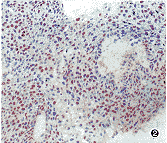

ras、p53、PCNA阳性染色均为棕褐色,分布在细胞的不同部位,ras蛋白染色在细胞浆,p53蛋白与PCNA染色在细胞核。阳性细胞呈灶状或弥漫分布(图1~3)。

图1 上颌窦鳞癌,ras p21阳性染色,染色部位在细胞浆.ABC×400 图2 上颌窦鳞癌,p53蛋白阳性染色,染色部位在细胞核.ABC×200 图3 上颌窦鳞癌,PCNA阳性染色,染色部位在细胞核.ABC×200